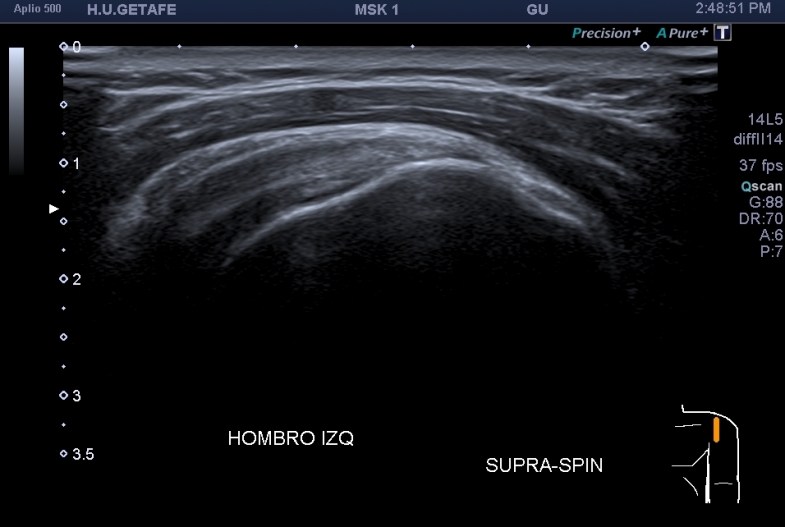

3.Tendón del supraespinoso

En esta parte del estudio te muestro un corte que a mi me parece vital, es el corte en eje largo del supraespinoso y la continuación hacia distal de la bursa apoyada en la cara anterior del húmero. Es una imagen preciosa en normalidad, y es maravillosa cuando nos muestra la bursa llena de líquido. Indicación de que el supraespinoso podría estar roto. Nunca dejes de realizar este corte, es muy importante y vas a encontrar patología en la Bursa en muchas ocasiones.